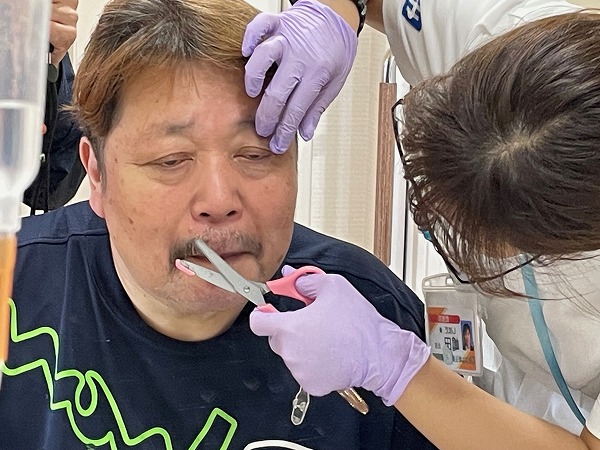

残すは、鼻の下の髭。”髭剃り名人”と言われる看護師さんが医療用の鋏を使って何とか剃っていく。病院だからカミソリなど刃物類は置いていないのである。この鋏では正直難しい。

最後は刃の付いてない電気カミソリ。でごしごし擦り付けるように剃っていった。もう何人もの髭を剃っているので感覚が分かっているのだそうだ。助かった手術室へこれで15分前に向える。